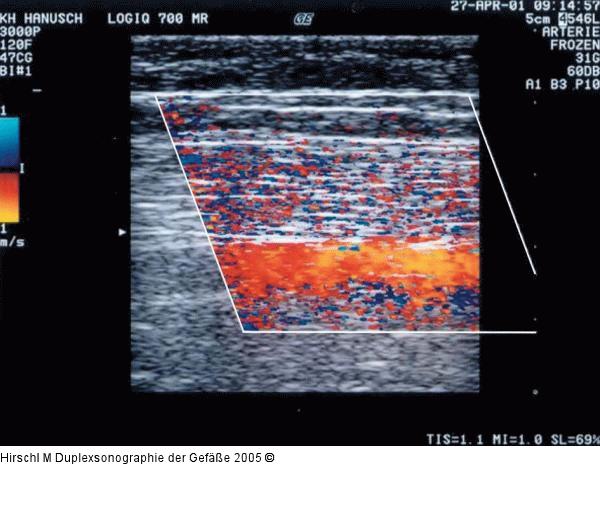

Abbildung 6: Duplexsonographie - Farbgain

Übersteuertes Farbgain: Farbe außerhalb des Gefäßes im Bereich des gesamten Farbfensters. |